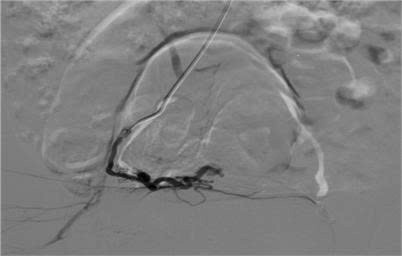

Sau can thiệp, tình trạng chảy máu âm đạo chấm dứt, bệnh nhân nhanh chóng ổn định và được chuyển về Bệnh viện Phụ sản Trung ương theo dõi, sau đó ra viện trong tình trạng khỏe mạnh, tái khám định kỳ ổn định.

Siêu âm là một phương tiện đầu tay hiệu quả để chẩn đoán cũng như tiên lượng các tổn thương AVM. Chụp mạch máu số hóa xóa nền (DSA) là tiêu chuẩn vàng trong chẩn đoán AVM và đồng thời việc nút chọn lọc các mạch máu tổn thương là biện pháp điều trị hiệu quả cho bệnh nhân.

ra-mau-2.jpg

Hình ảnh kiểm tra sau nút mạch - Ảnh BVCC